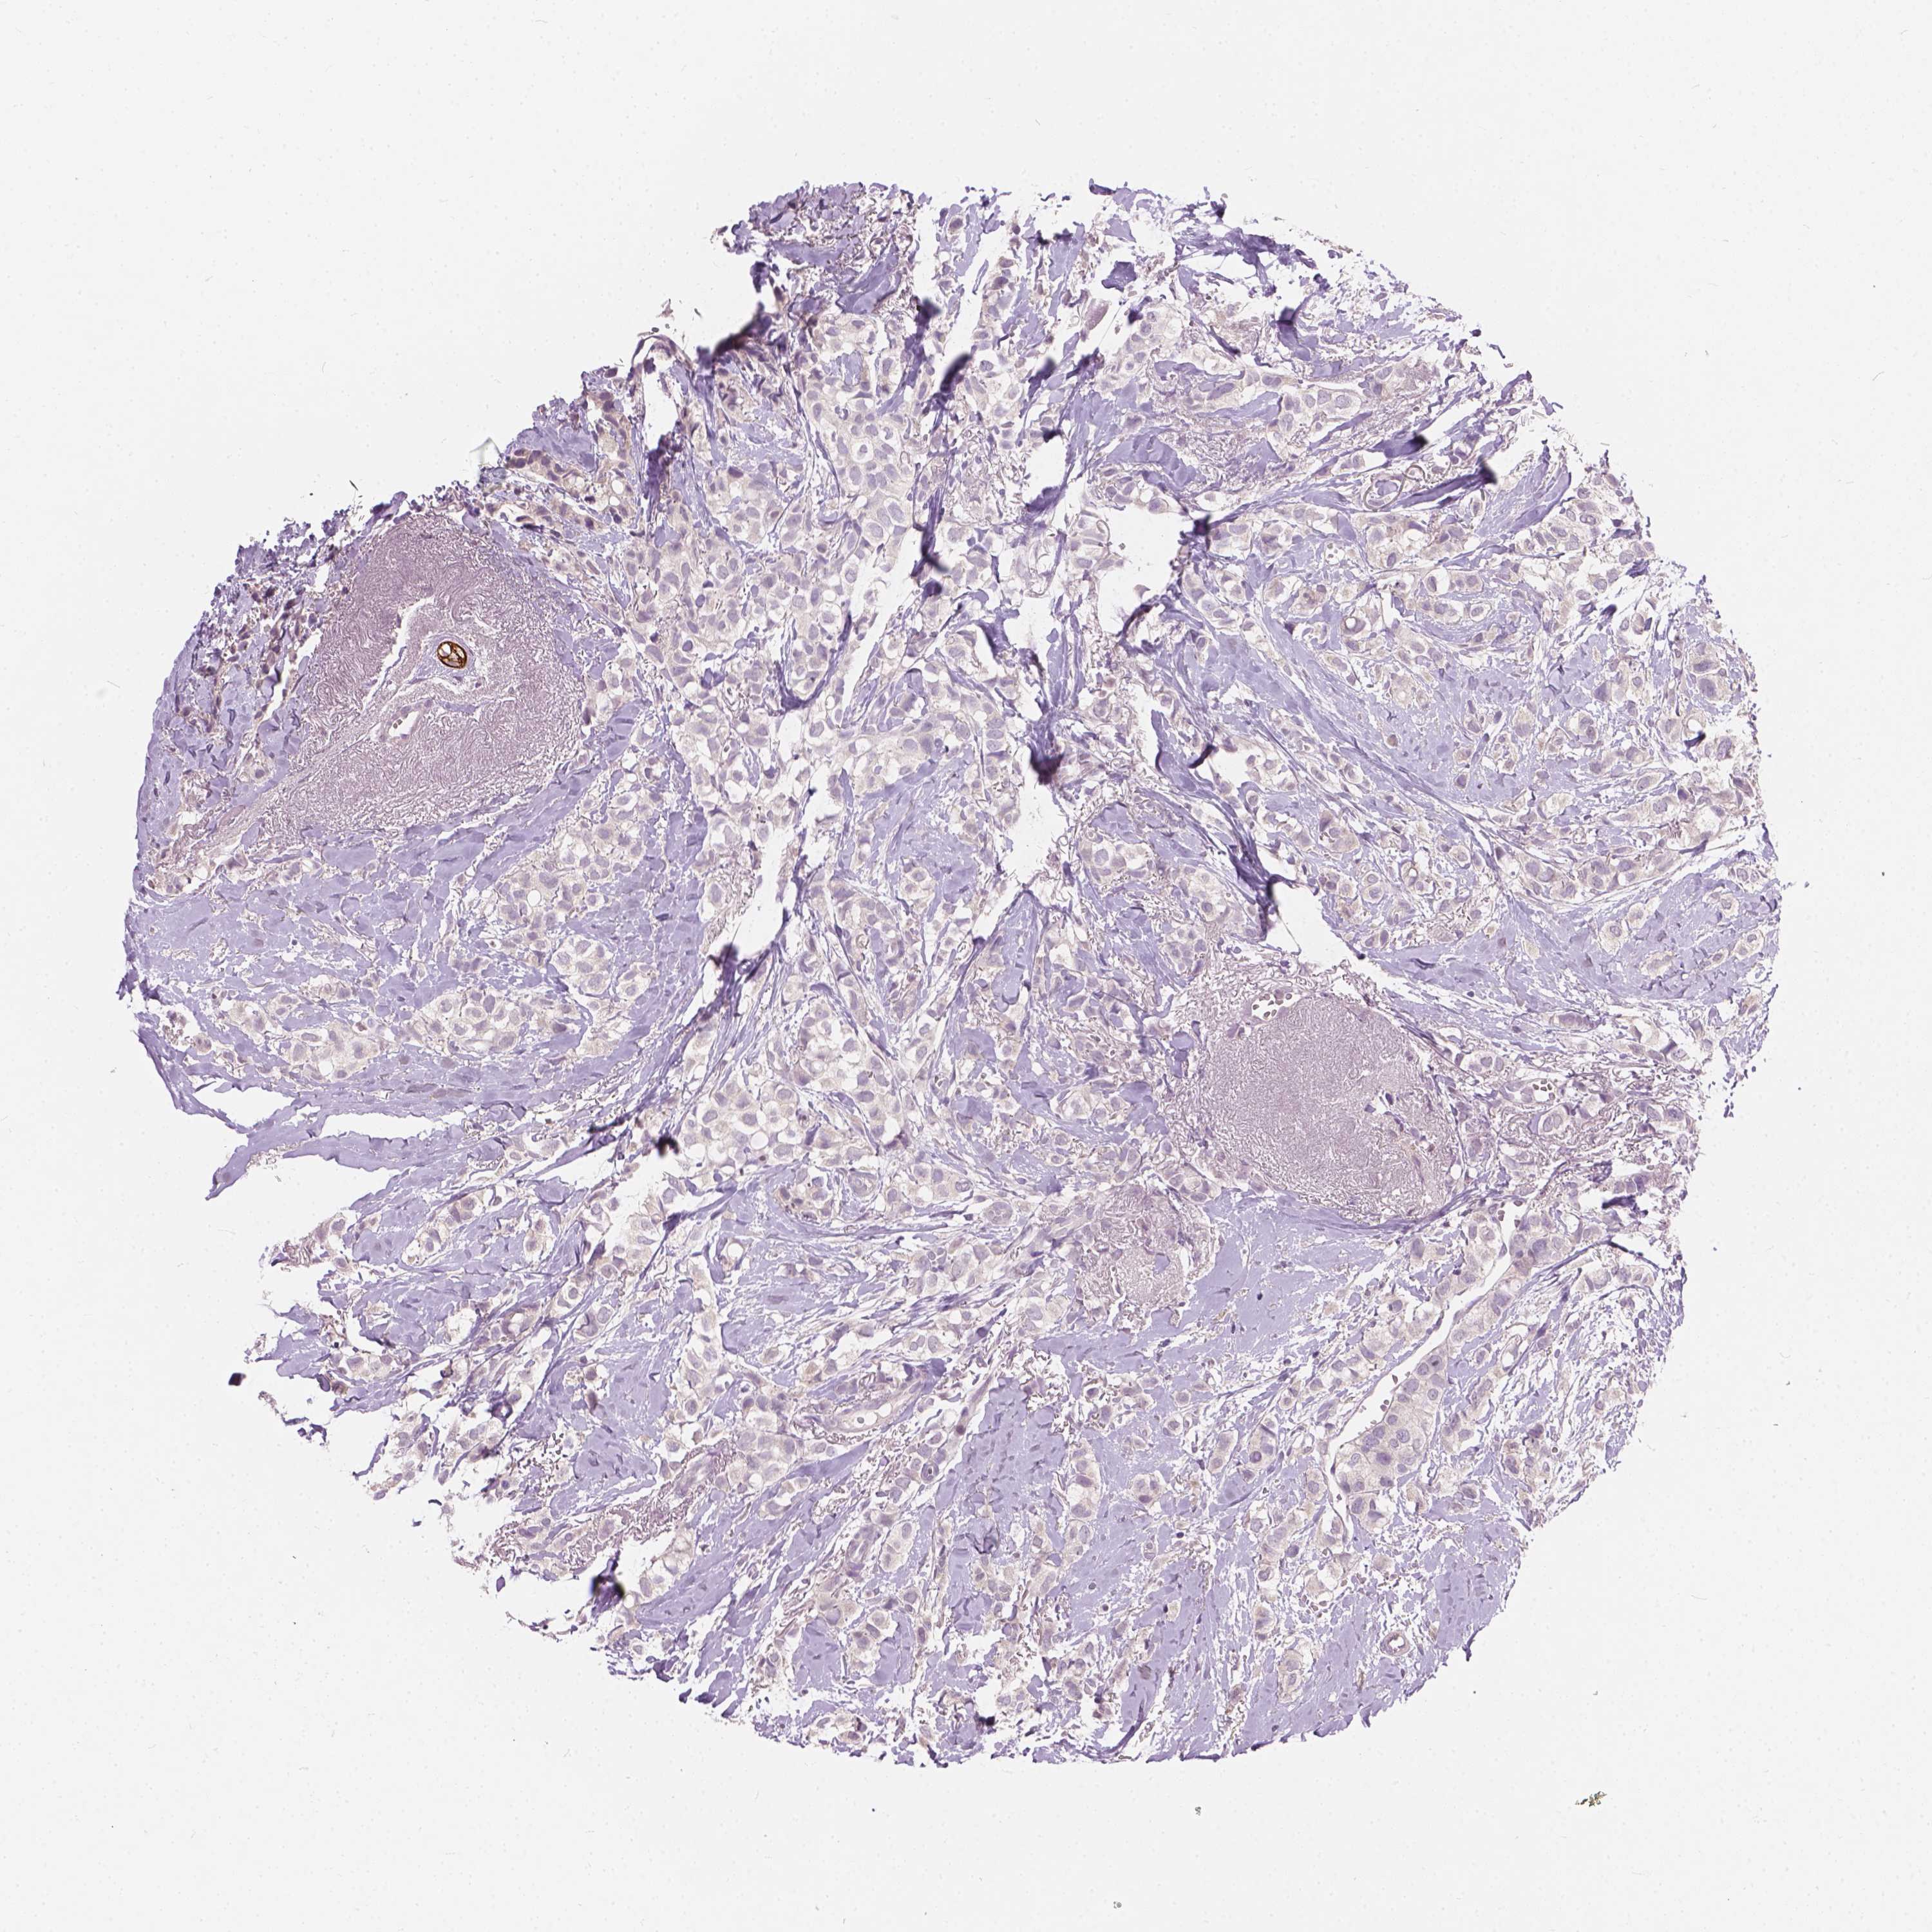

KRT17

CANCER BREAST CANCER Show tissue menu

BRCA TCGA BRCA VALIDATION PROTEIN EXPRESSION

ANTIBODIES

AND

VALIDATION